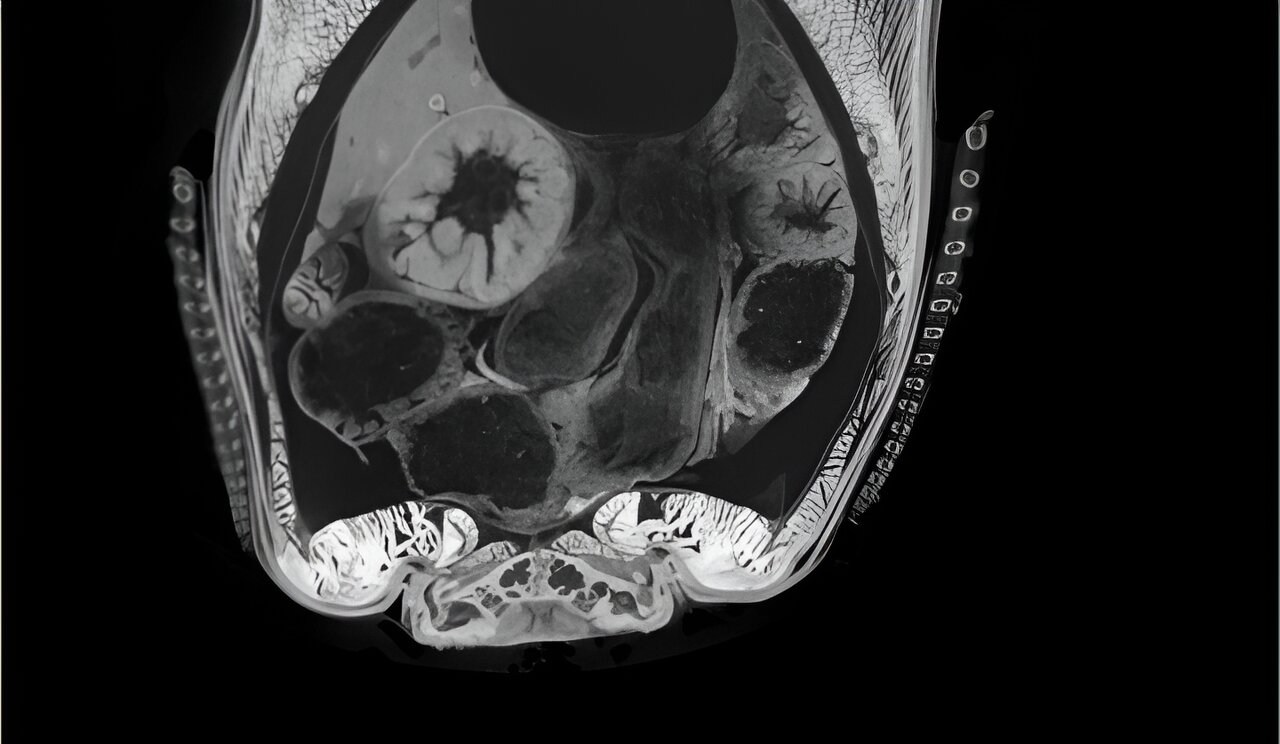

"The µCT has an X-ray source and a microscopic detector that picks up the signal. Because we were interested in soft tissue, we used iodine to give the soft tissue a better contrast on the images," explains Dr. Ziadi-Künzli.

With this method, the team imaged various fish, starting with the mudskipper and its close evolutionary relatives. For comparison, the researchers also scanned other fish, for example the zebrafish, which are only distantly related to the mudskipper.

With the initial imaging complete, the hardest part of the study was about to begin: The analysis of the thousands of separate images produced by the µCT. "We had to manually sort through all those images to identify each tissue. Basically, we have been working on the analysis since 2019," notes Dr. Ziadi-Künzli.

After scanning the different fish, Dr. Ziadi-Künzli worked on images such as this to identify the different organs and tissues including muscles, bones, cartilage and tendons, inside the animals' bodies. Credit: Dr. Fabienne Ziadi-Künzli/OIST, Image taken with Thermo Fisher Scientific‘s AMIRA Software